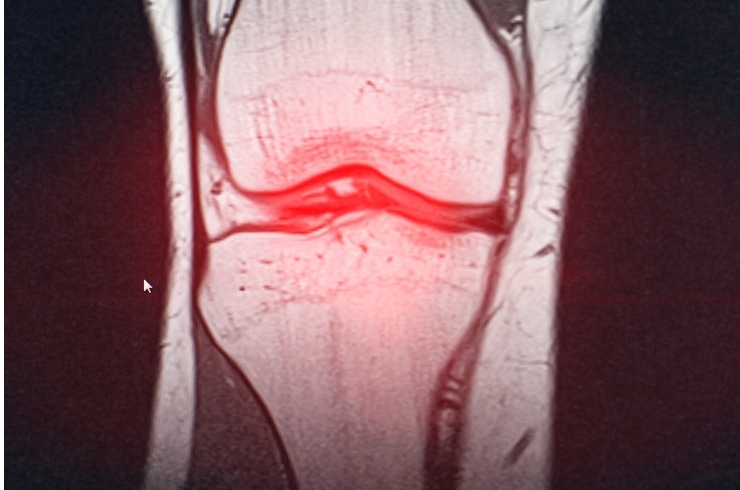

Comprehensive evaluation and treatment for knee conditions, relieving pain, restoring stability, improving mobility, and supporting long-term joint health effectively.

Minimally invasive knee procedures to repair ligaments, restore stability, reduce pain, and enable faster functional recovery.

Advanced techniques to repair meniscus and preserve cartilage, preventing degeneration and maintaining long-term joint health.

MRI is recommended for persistent pain, instability, swelling, or suspected ligament and cartilage injuries.